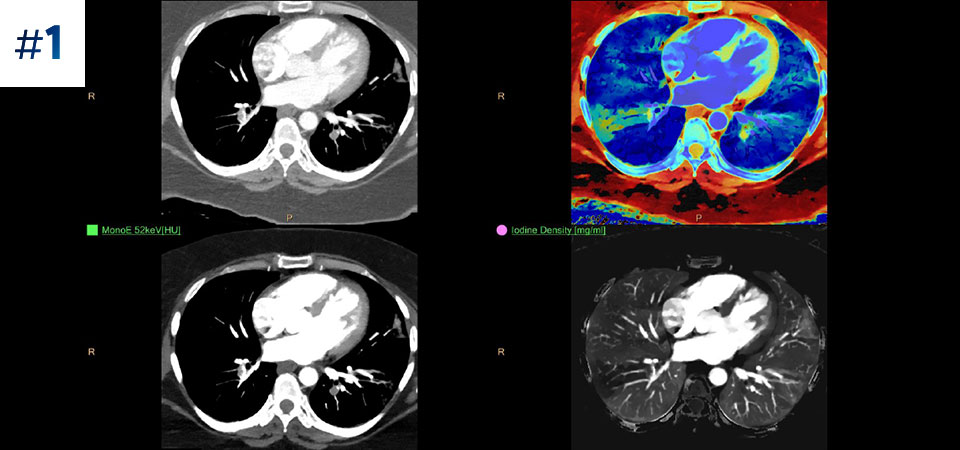

Pacjenci o różnych typach budowy ciała Możliwość przeprowadzania badań u pacjentów różnej wielkości, od dzieci po osoby otyłe.

Ograniczenie liczby ponownych badań Udoskonalona charakterystyka i wizualizacja tkanek może ograniczyć konieczność wykonywania ponownych badań, jaka zachodzi w przypadku badań o niezadowalającej jakości oraz przypadkowych obserwacji.

Nie ograniczaj się do konwencjonalnej tomografii komputerowej. Zobacz, jak wyniki uzyskane dzięki warstwom detektora spektralnego mogą zwiększyć pewność diagnostyczną.

Zobacz różnicę pomiędzy tomografią komputerową opartą na detektorze spektralnym a konwencjonalną tomografią komputerową

Zobacz jak tomograf spektralny pomaga w diagnostyce pacjentów onkologicznych.